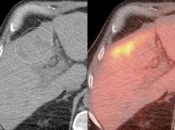

Assessing Response to Therapy & Prognosis:

- Early Response: Non-responders can be offered alternative therapy.

- Late Response: Assess success or failure of therapy, and ultimate outcome.

Recurrence & Restaging:

- Restaging suspected recurrence.

- Distinguishing recurrence from post-therapeutic inflammation.